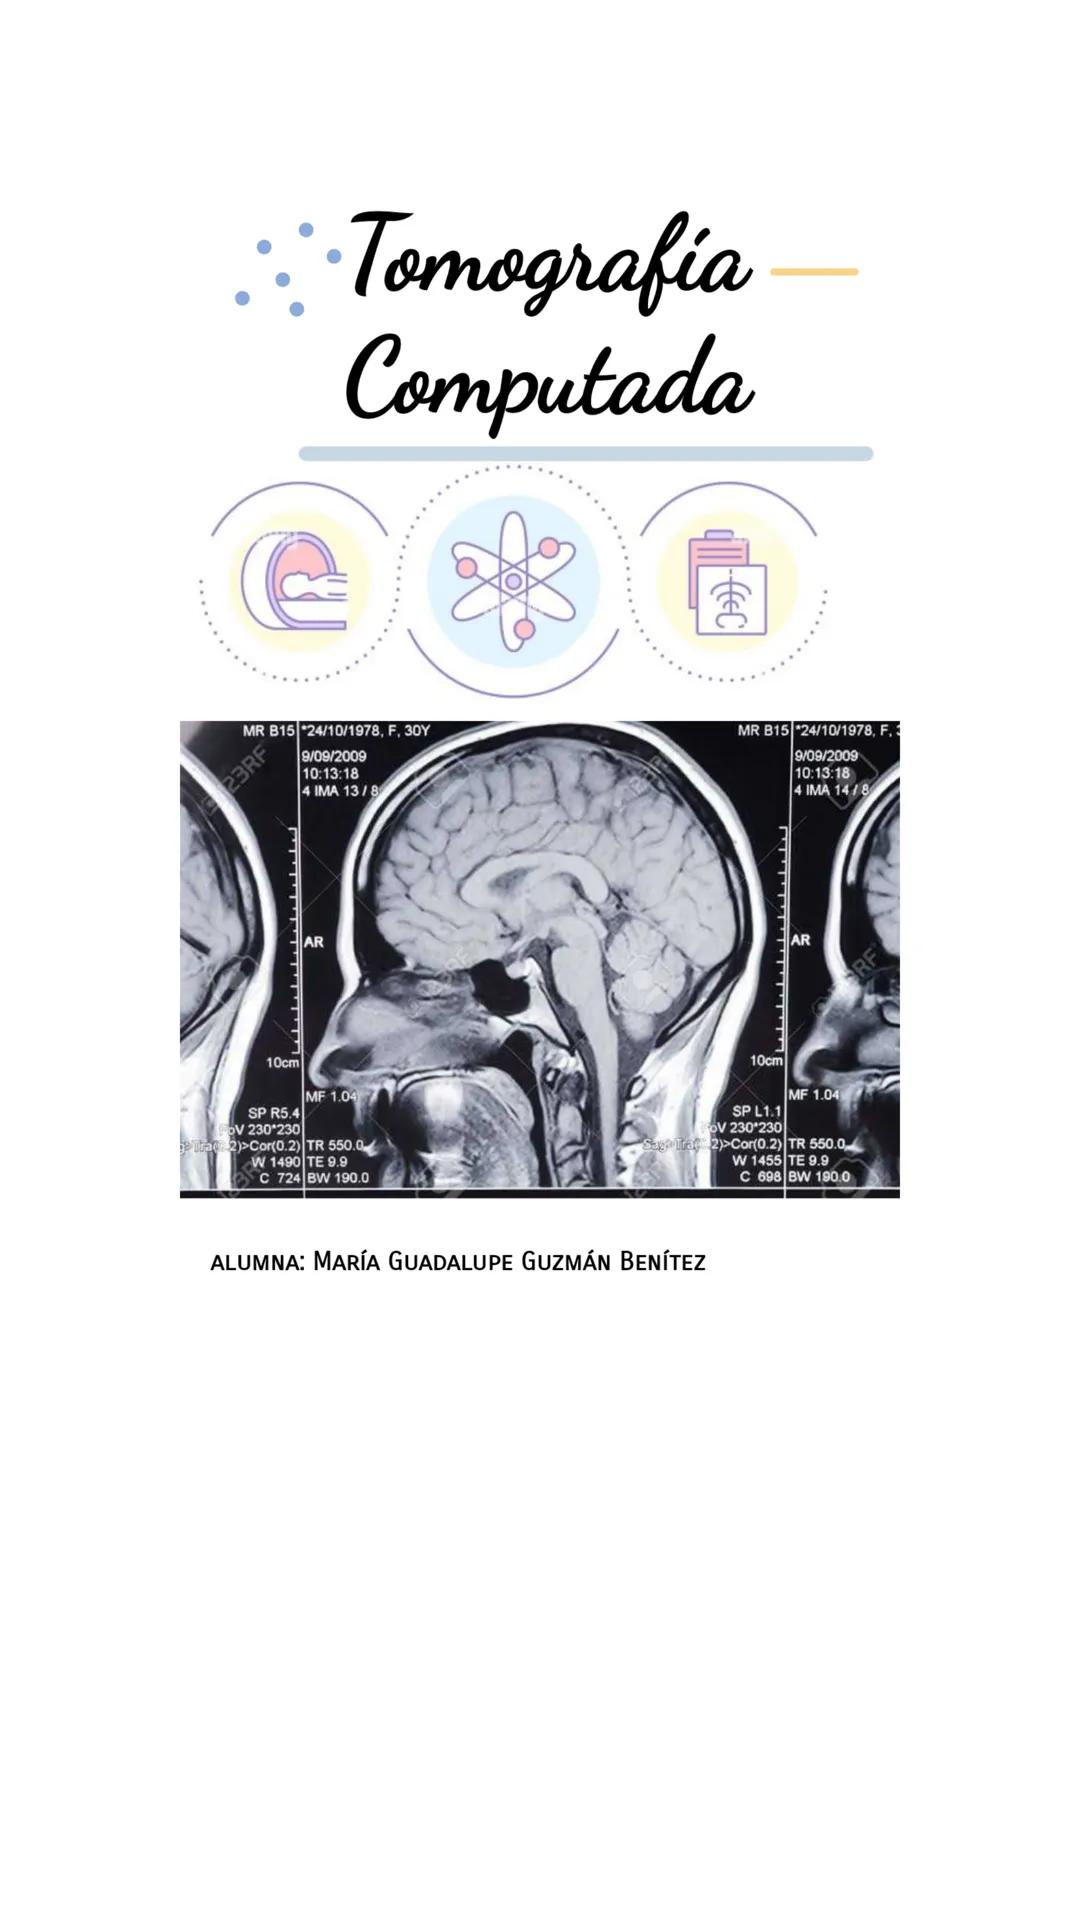

La tomografía computada es una técnica avanzada de diagnóstico por imagen que permite ver el interior del cuerpo en detalle. A diferencia de las radiografías convencionales, la TC produce imágenes en "rebanadas" o cortes anatómicos.

En las imágenes podemos observar ejemplos de cortes tomográficos de distintos planos. Cada imagen proporciona información específica sobre las estructuras internas del paciente, permitiendo a los médicos observar detalles que podrían pasar desapercibidos en otros estudios.

💡 La ventaja principal de la TC es que permite visualizar simultáneamente tejidos blandos, huesos y vasos sanguíneos en una sola exploración, algo que no es posible con radiografías convencionales.